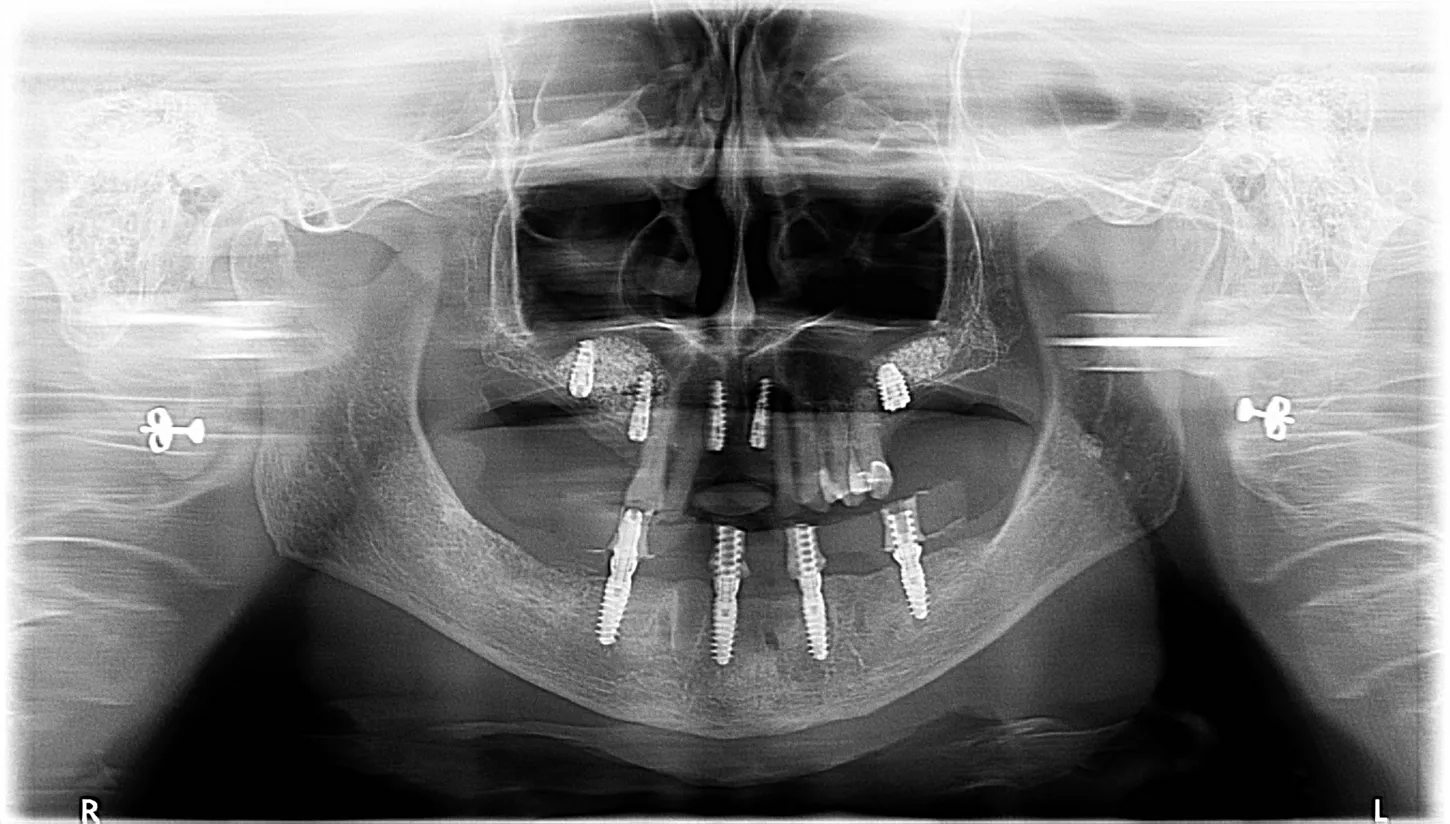

12.  The postoperative OPG shows the implant placement as planned

17.  Final control OPG with the complete treatment of the upper and lower jaw.